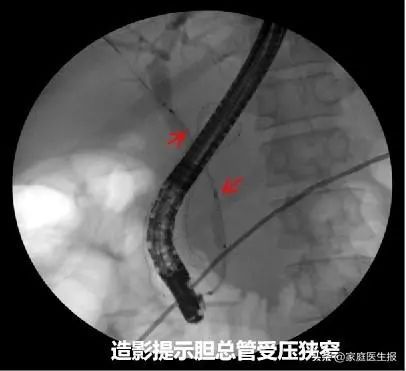

术中,熊光苏带领团队首先通过球囊扩张狭窄变形幽门部,进入十二指肠球部发现肿瘤已浸润导致管腔狭窄。直视下运用取石球囊带导丝越过狭窄段,注入造影剂肠腔显影,球囊打开后回拉至狭窄处,明确狭窄段长度。X光引导下成功置入长度60mm、直径26mm的金属支架,整个过程仅耗时15分钟。

内镜虽然可顺利通过十二指肠狭窄处,可是又遇到了新的难题:支架挡住了十二指肠乳头,暴露乳头及尝试ERCP插管困难。熊光苏带领ERCP团队耐心调整内镜视野,在金属支架网孔中寻找到乳头。经预切开、插管、造影、胆道扩张、支架置入等一系列操作,最终成功引流出黑色胆汁。